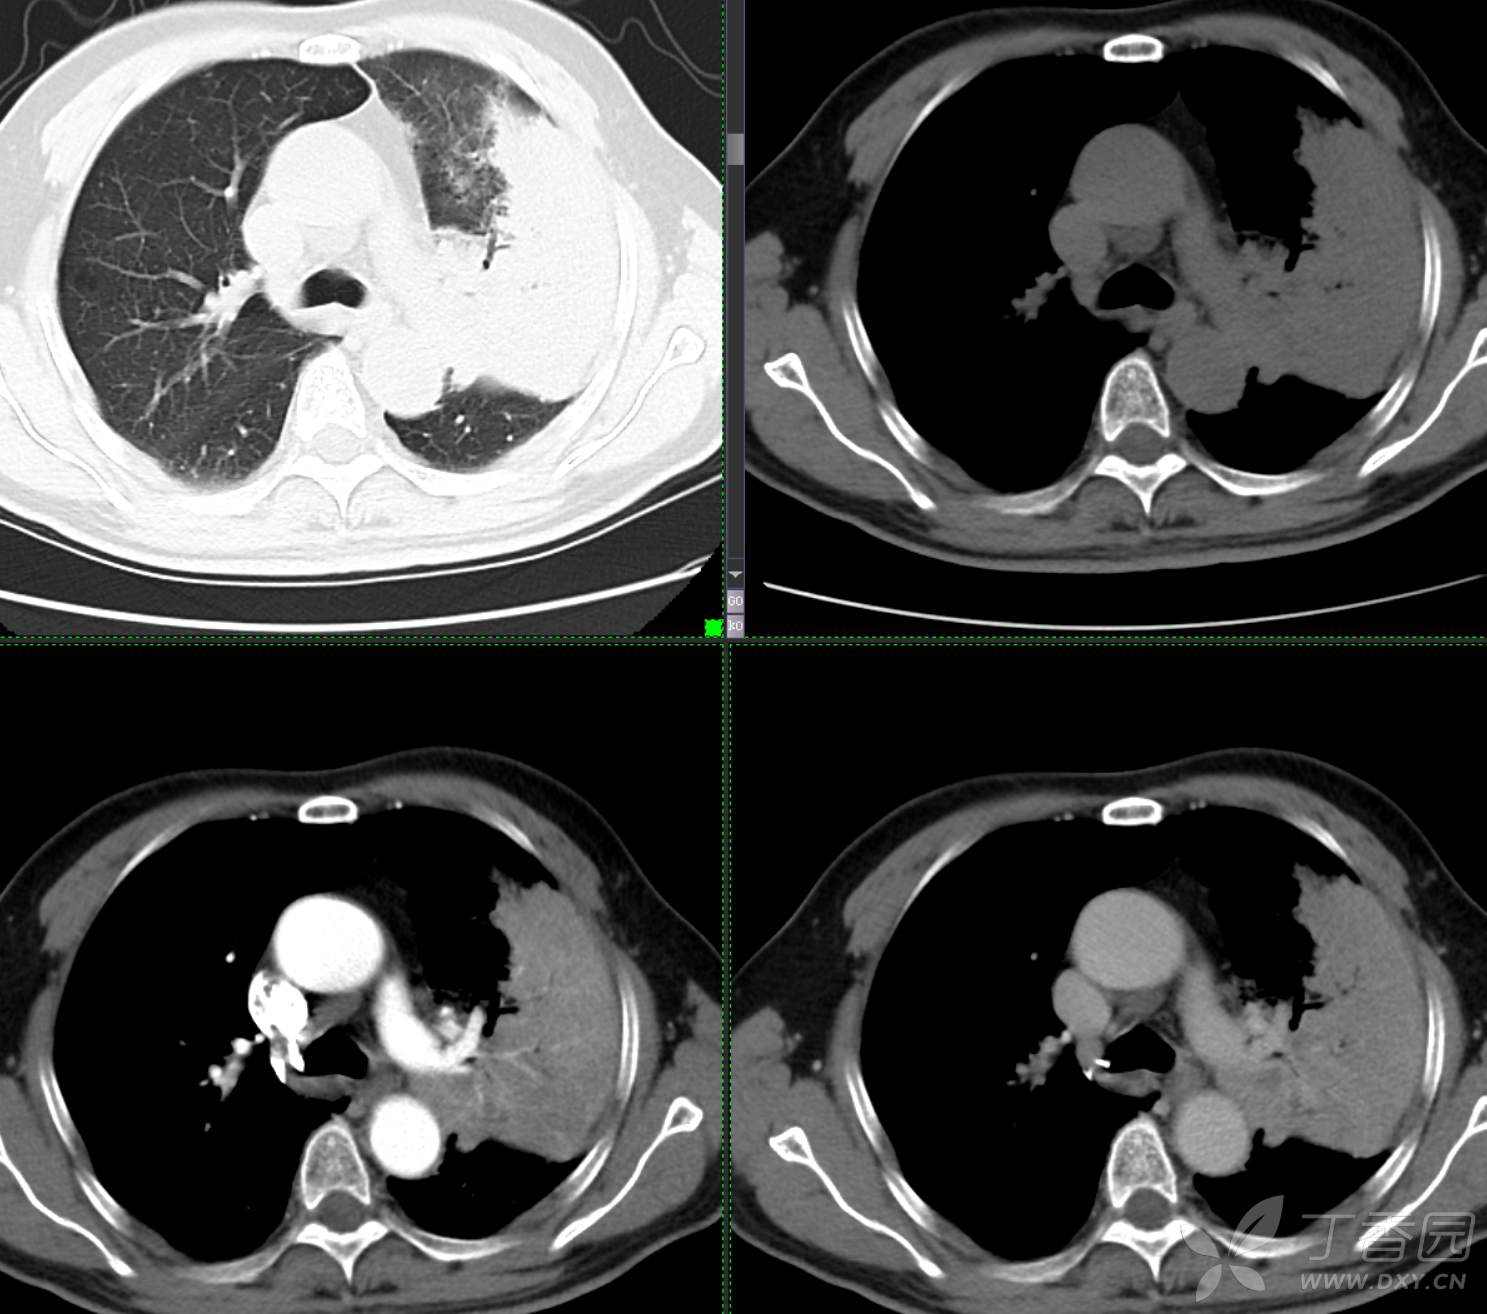

胸部29:大叶性病变,有征象,有特点,你的诊断?

患者性别:男

患者年龄:65

主诉:咳嗽2月余

简要病史:患者2月余前无明显诱因下出现咳嗽,干咳为主,夜间加重,伴咳痰,量中等,白粘痰为主,无明显胸闷气促,无恶心呕吐,无鼻后滴液,无发热畏寒,无鼻塞流涕不话,患者至当地医院就诊,考虑肺部感染,住院治疗,先后予“哌拉西林他挫巴坦针、莫西沙星针、美罗培南针、亚胺培南针、利奈唑胺片”抗感染治疗,患者咳嗽症状稍有好转,但仍存,为进一步诊治至我院门诊,现为进一步诊治,拟“肺部阴影、肺部感染”收治入院。